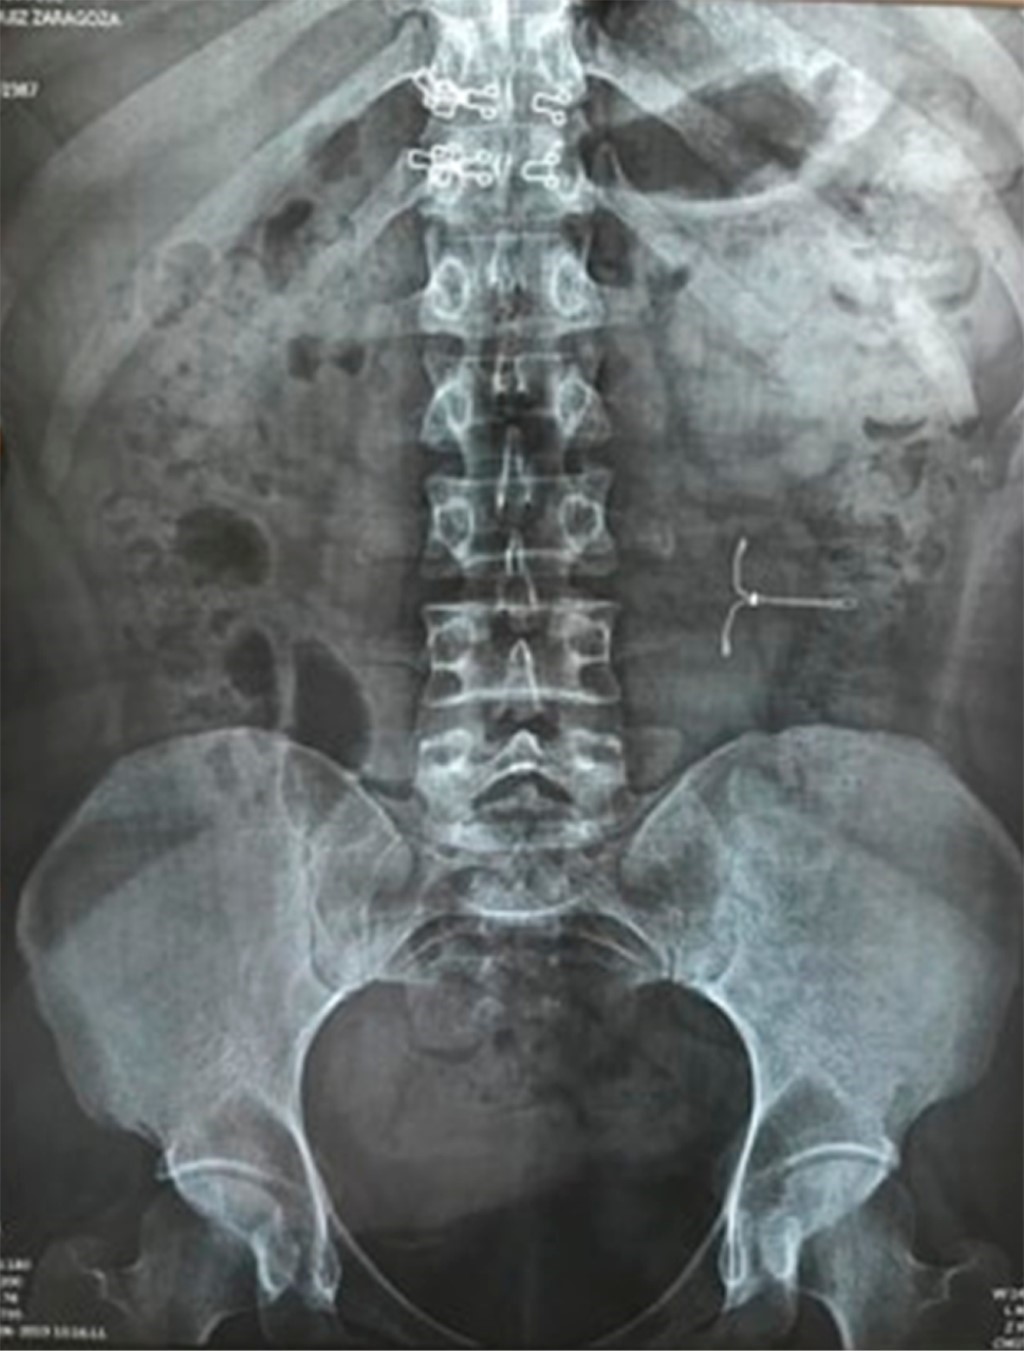

Mujer de 33 años con cesárea cuatro años previos y colocación de dispositivo intrauterino hormonal con levonorgestrel después de un mes. Tres años posterior a la colocación acude a revisión por síntomas inespecíficos pélvicos y descarga vaginal frecuente, con mejoría parcial tras tratamiento. Meses después se decide realizar extracción del dispositivo intrauterino guiado por ultrasonido sin localizarlo en pelvis. Se indicó una radiografía de abdomen localizando el dispositivo fuera de la cavidad uterina a nivel de flanco izquierdo sin datos de aire o líquido libre en cavidad (Figura 1). Se programa laparoscopia para extracción de dispositivo tres semanas después. Bajo anestesia general y técnica estéril se realizó laparoscopia para abordar hemiabdomen izquierdo, encontrando el DIU adherido al omento mayor sin erosión a estructuras adyacentes. Se resecó epiplón circundante con energía ultrasónica para sellar vasos sanguíneos, extrayendo dispositivo a través de un puerto sin complicaciones (Figuras 2 y 3). Cursó el postoperatorio con signos vitales estables sin eventualidades, iniciando dieta a las 24 horas postoperatorias, con evacuaciones presentes posteriormente y alta a domicilio tras adecuado manejo del dolor.

Figura 1